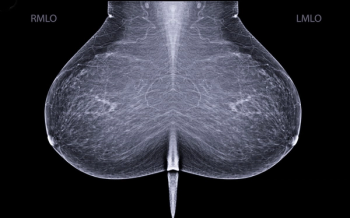

For women with dense breasts, the combination of mammography and supplemental breast ultrasound had a 36.4 percent higher sensitivity rate for detecting breast cancer in comparison to the combination of mammography and adjunctive AI, according to a new study.